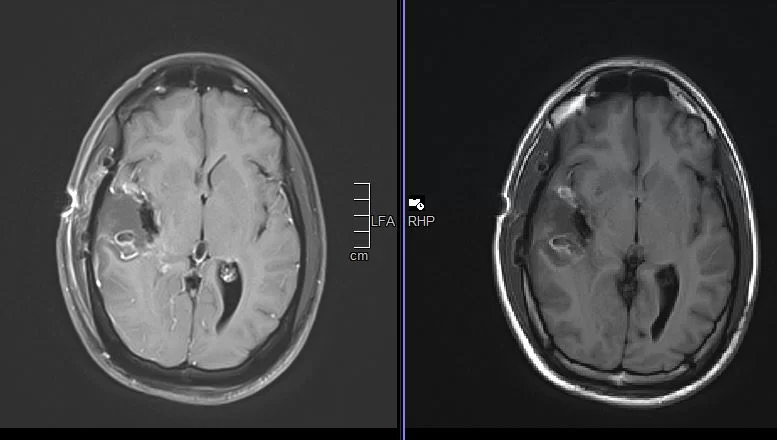

H Μαγνητική Τομογραφία εγκεφάλου ανέδειξε εκτεταμένη χωροκατακτητική εξεργασία δεξιά κροταφικά με πίεση επί του σύστοιχου κροταφικού κέρατος και σημαντικό περιεστιακό οίδημα.

Η μετεγχειρητική μαγνητική τομογραφία εγκεφάλου ανέδειξε ολική εξαίρεση του σκιαγραφούμενου όγκου.